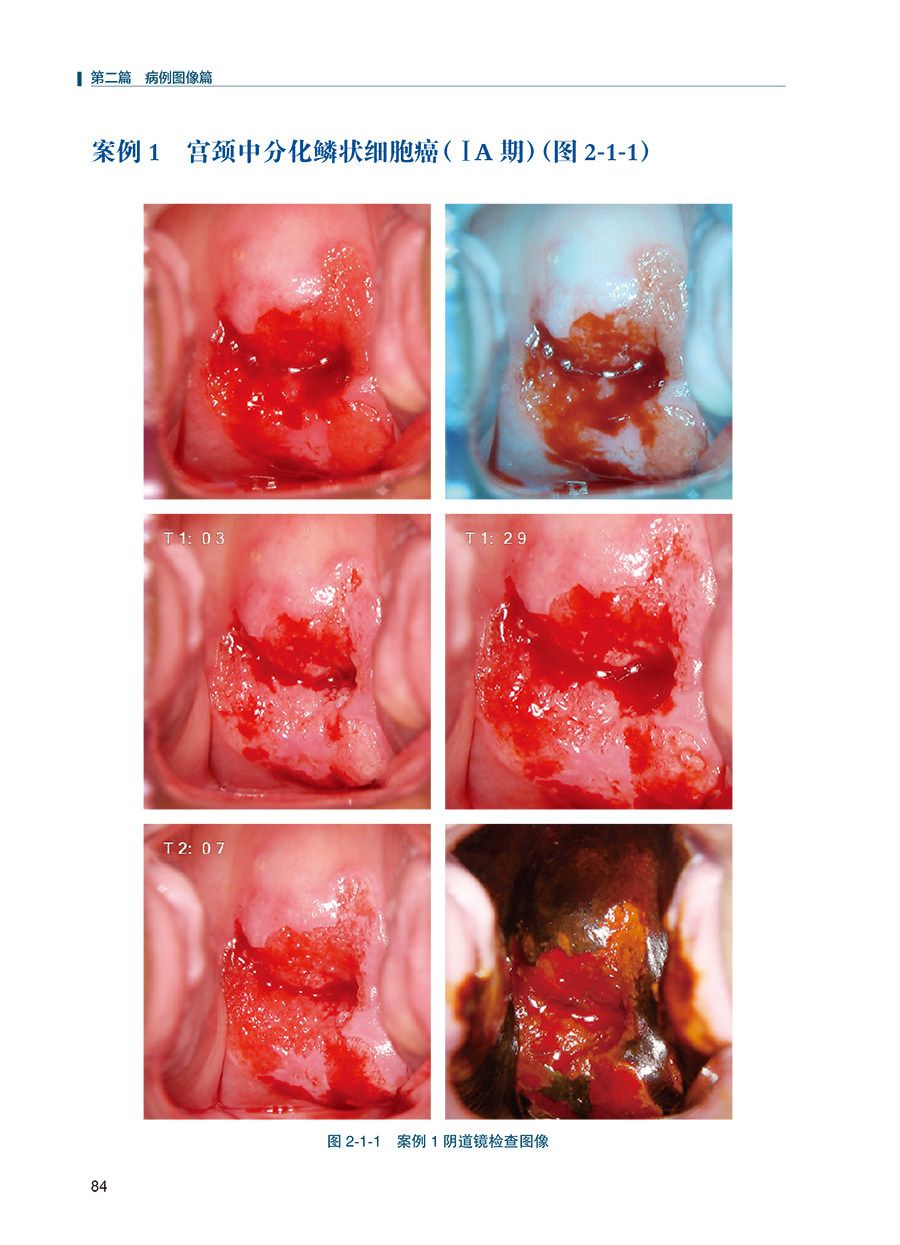

本书系统地对R-way阴道镜诊断路径做了详细的介绍,包括宫颈病变的病理组织学基础、R-way阴道镜诊断路径术语、操作方法和鉴别诊断。主要内容包括阴道镜下宫颈癌、高级别病变、低级别病变及正常阴道镜所见共100例病例,其中每一例均包括宫颈脱落细胞学、人乳头瘤病毒检测、阴道镜图谱及组织病理学结果。另附加作者对案例诊断路径的解读。诊断流程图文并茂、思路清晰,各种诊断信息完善,最终提供组织病理学结果。读者学习后相当于自己完成100例阴道镜检查诊断,对今后的阴道镜的诊断水平将有大幅度提升。